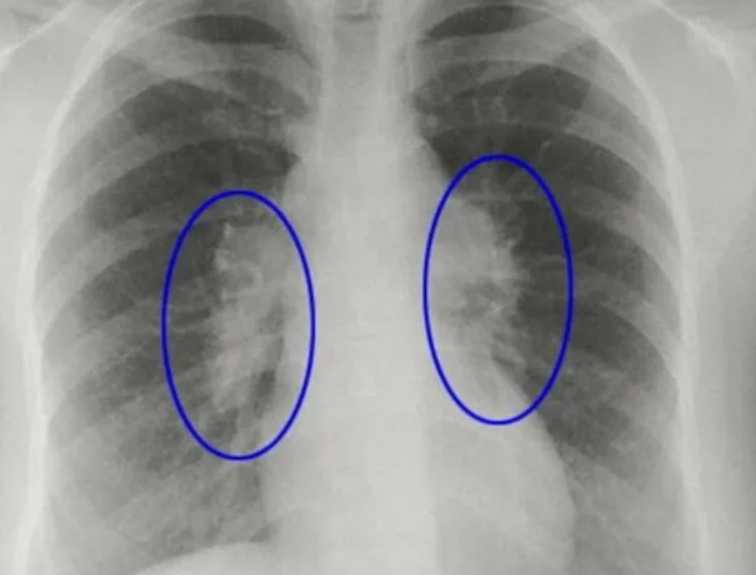

Некоторые типы пневмонии приводят к суставным, головным болям, образованию красных пятен на лице, шее. При обследовании врач замечает хрипы в легких. В этом случае нужна дополнительная диагностика — рентген, КТ.

Чтобы точно убедиться в наличии пневмонии без температуры, поставить точный диагноз, специалист выслушивает жалобы пациента, осматривает грудную клетку, проверяет симметричность дыхания. Прослушивание легких позволяет выявить хрипы, а больные участки во время простукивания издают приглушенный звук.

Еще требуется анализ крови, мочи и мокроты. Рентген поможет выявить очаг воспаления в легких, его масштабы. Если есть подозрения на этот недуг, нужно сразу же обратиться к врачу. Самостоятельно поставить себе диагноз не получится. В больнице проводится полное обследование, что поможет точно определить вид заболевания.